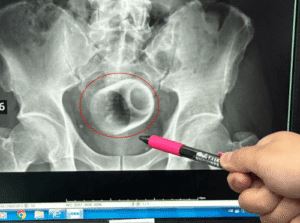

Врачи использовали презерватив, чтобы вытащить зажигалку из желудка пациента

Житель Чэнду (провинция Сычуань, Китай) не особенно обращал внимание на то, что у него периодически болел живот. Но когда боли...